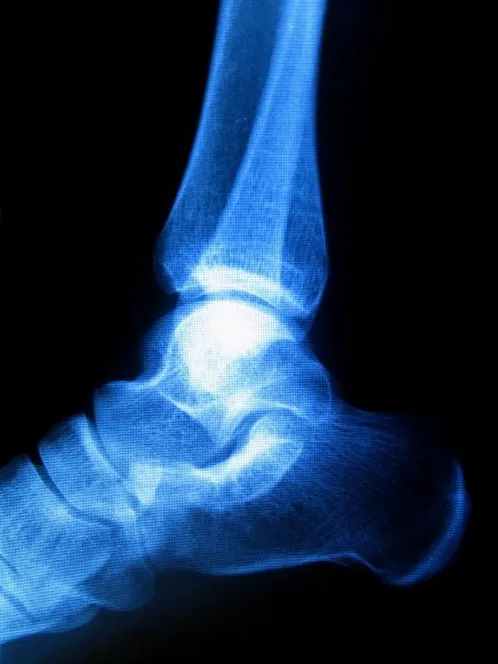

Haglund's Deformity

haglunds deformity Sometimes known as “pump bump” because of its prevalence among women who wear pump-style shoes, Haglund's deformity can occur in one or both of the feet. If you are suffering from Haglund's deformity you will most likely have noticed a bony enlargement at the back of the heel. This inflammation is caused when the bursa, a fluid­-filled sac between the Achilles tendon and your heel bone, becomes irritated. Other signs of Haglund's deformity include pain where the Achilles tendon and the heel meet, swelling, and redness.

While genetic factors influence your likelihood to develop Haglund’s deformity (high arches, a tight Achilles tendon), stiff shoes are also a major risk factor.